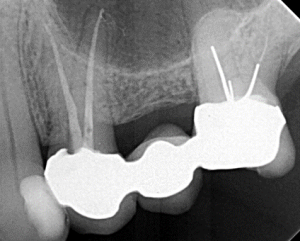

Root Canal / Retreatment

Clinical Cases